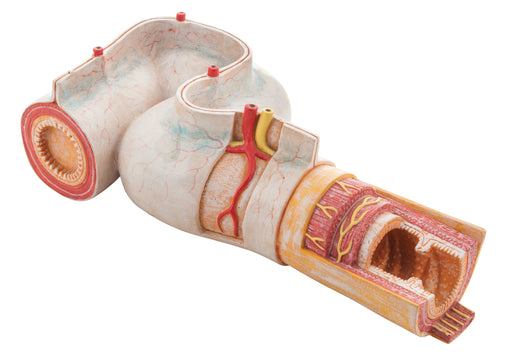

Intestinal Jejunum Cutaway

The small intestine is responsible for most of the absorption of nutrients from food, with the absorption occurring mostly in the duodenum and jeju...

View full detailsAM16050 -